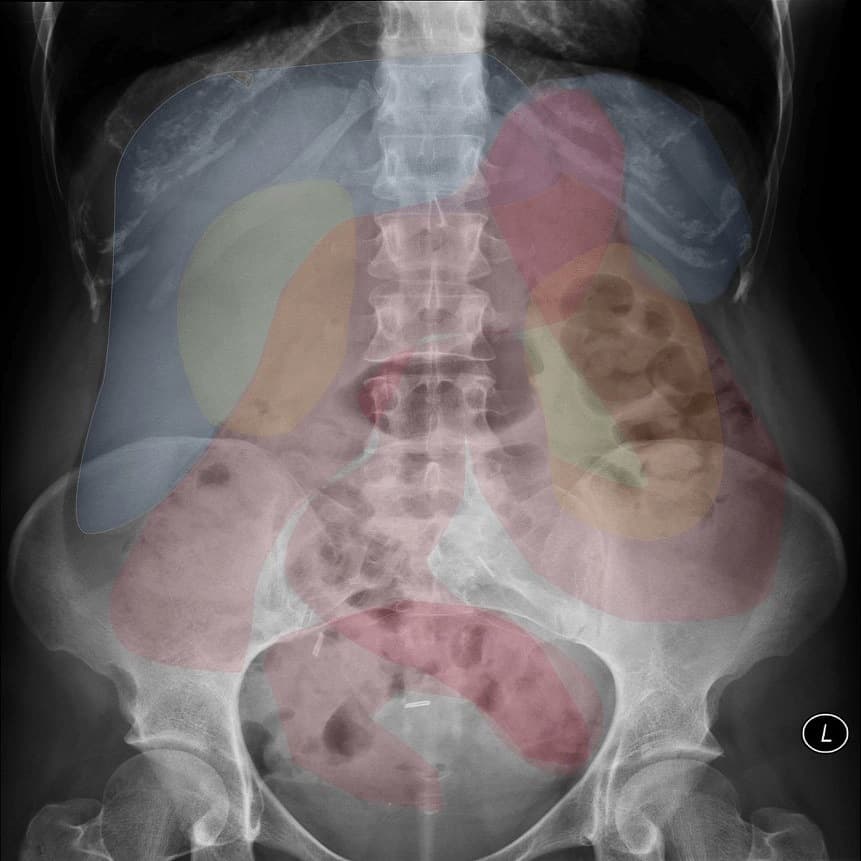

II. Giải phẫu

– Thận hình hạt đậu nằm phía sau ổ phúc mạc, 2 bên cột sống.

– Cấu tạo thận: xoang thận ở giữa – xung quanh là nhu mô thận (vỏ thận + tủy thận)

+ Xoang thận: chứa mạch máu và thần kinh thận, hệ thống đài bể thận và mô liên kết mỡ. Đài thận nhỏ nhận nước tiểu từ nhú thận, đổ ra đài thận lớn, đài thận lớn hợp thành bể thận – nối với niệu quản.

+ Vỏ thận: nằm ngay dưới bao thận, gồm cột thận (giữa các tháp thận) và các tiểu thùy vỏ từ đáy tháp thận tới bao thận.

+ Tủy thận: do các tháp thận (tháp Malpighi) tạo nên. Đáy tháp thận hướng về phía vỏ thận, đỉnh hướng về phía xoang thận, lồi vào trong xoang thận tạo nên nhú thận – nối với đài thận nhỏ.

– Thận xoa trục, 2 cực dưới thận liên tục với nhau vắt ngang qua phía trước cột sống bởi nhu mô thận hay tổ chức xơ.

– Trên lát cắt ngang qua đường giữa: 2 thận dính nhau, vắt ngang qua cột sống, phía trước động mạch chủ bụng.

– Trong trường hợp điển hình thấy hình ảnh bóng 2 thận xoay trục với cực dưới hướng vào trong phía cột sống, gần nhau, cực trên xa nhau.

– Hai thận xoay trục, cực dưới hướng vào trong phía cột sống.

– Đài bể thận bình thường hướng lên trên ra ngoài => hướng xuống dưới.

– Phần nối hai cực dưới là nhu mô hoặc dải xơ vắt ngang phía trước cột sống.